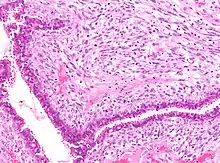

![]() | Fibroblasts | Fibroblasts in intestinal pneumonia | Category: Fibroblasts | Fibroblast |